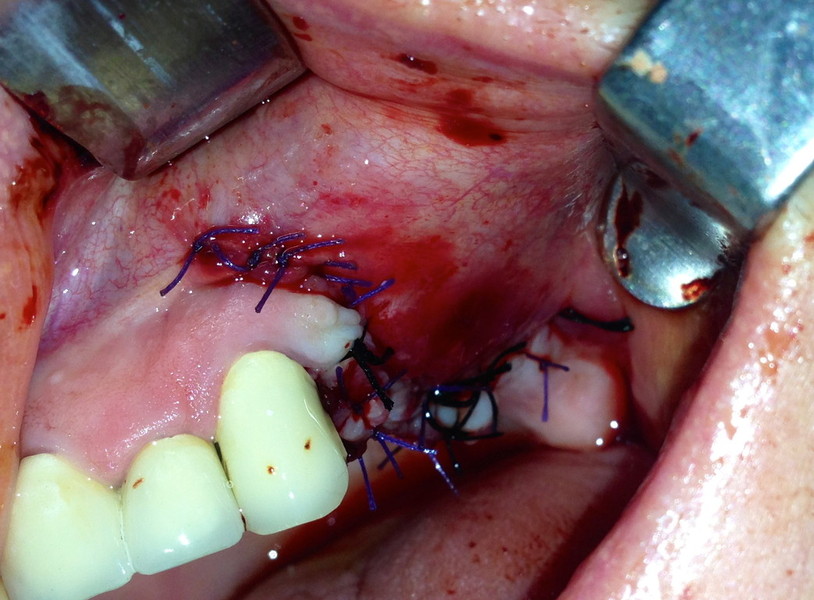

Impianti Post-estrattivi con innesto di osso e tessuto epitelio-connettivale